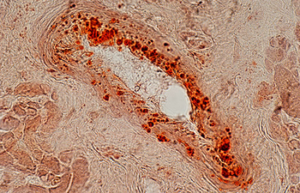

- Differentiation of cultured cells into different cell lines

- Confirmation of the nature of differentiated cells by ICC method

- Cell transplant from blood as IP, sub-kidney and muscle capsule

- Tracking of transplanted cells